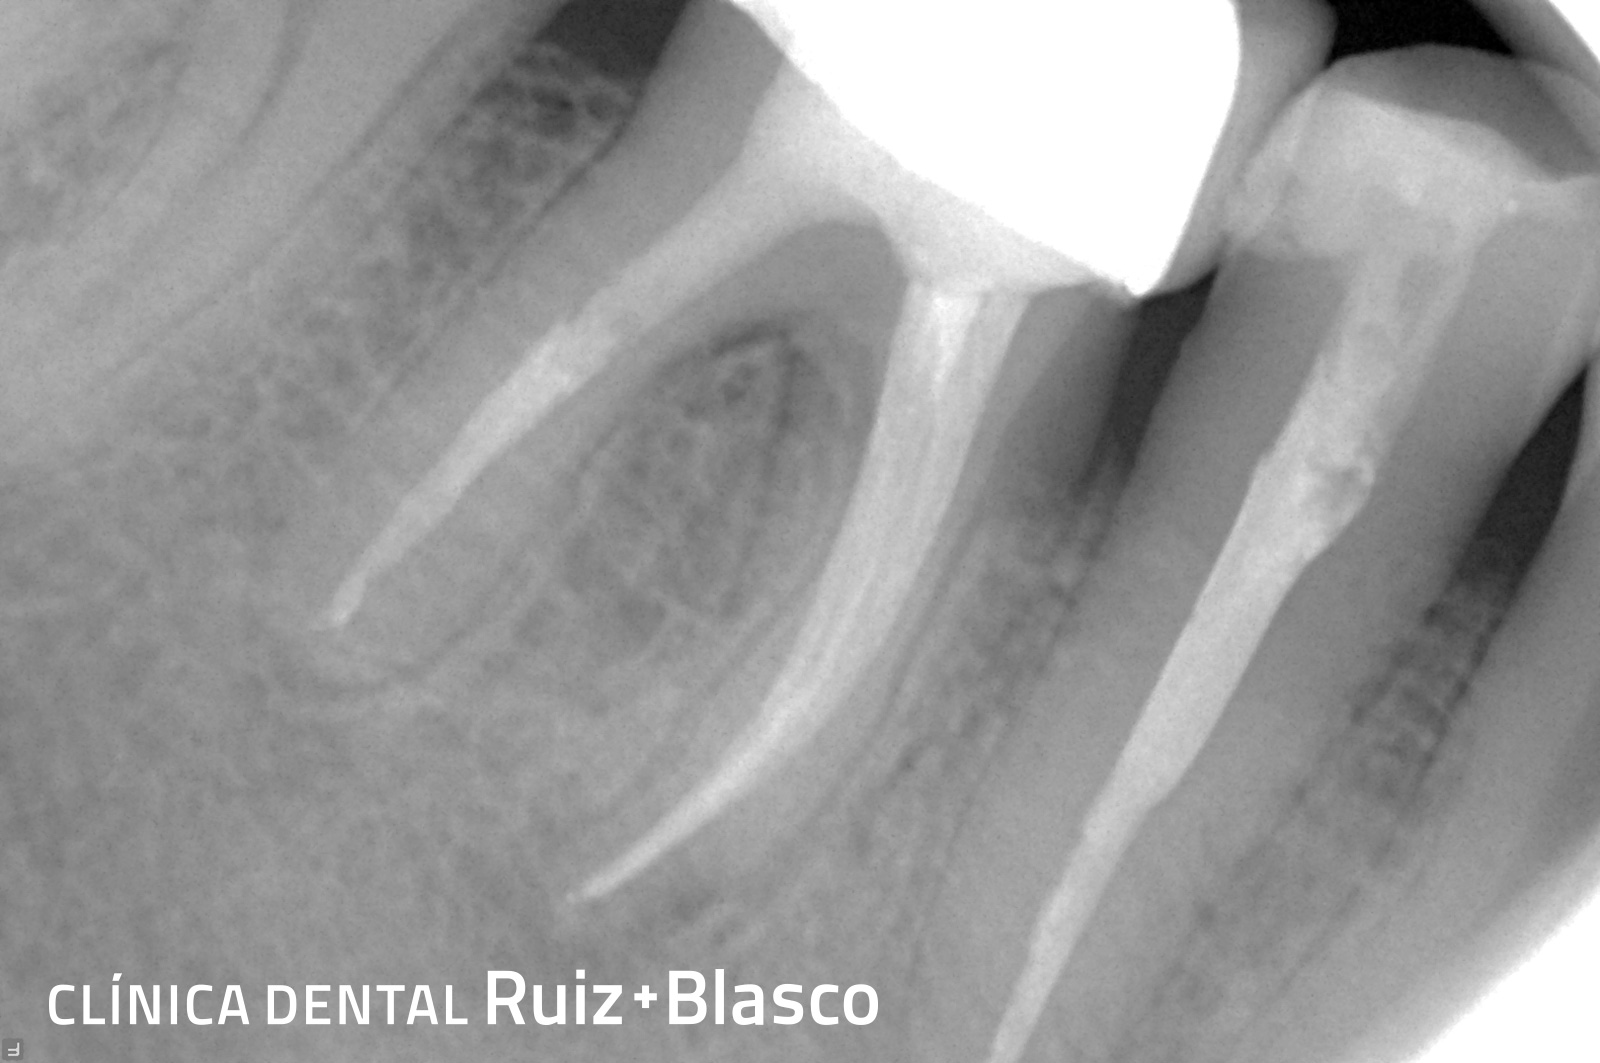

Caso 2

En este caso se puede contemplar el retratamiento de una endodoncia que no ha dado buen resultado y, por ello, había generado una lesión apical. Se puede observar cómo la lesión comienza a desaparecer después del retratamiento.